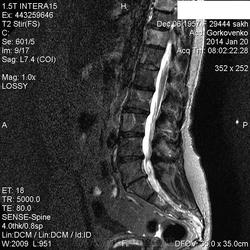

Первая пациентка:

В телах позвонков определяются множественные очаги и фокусы разной степени интенсивности понижения МР-сигнала по Т1, Т2 ( первые 2 картинки), неоднородного повышения по Т2 с жироподавлением ( третьи картинки).

Контрастирование  не проводили.